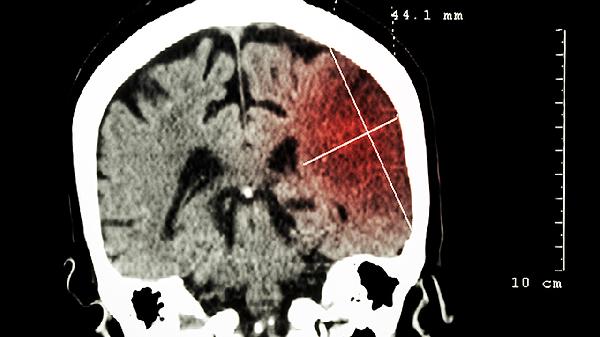

脑部疾病如脑肿瘤、脑卒中、多发性硬化等,也可能导致视力模糊。脑肿瘤压迫视神经或视觉中枢,会影响视力。脑卒中可能损害视觉通路,导致视野缺损或视力下降。多发性硬化是一种自身免疫性疾病,可能影响视神经,引起视力模糊。这些疾病通常伴随其他症状,如头痛、恶心、肢体无力等。